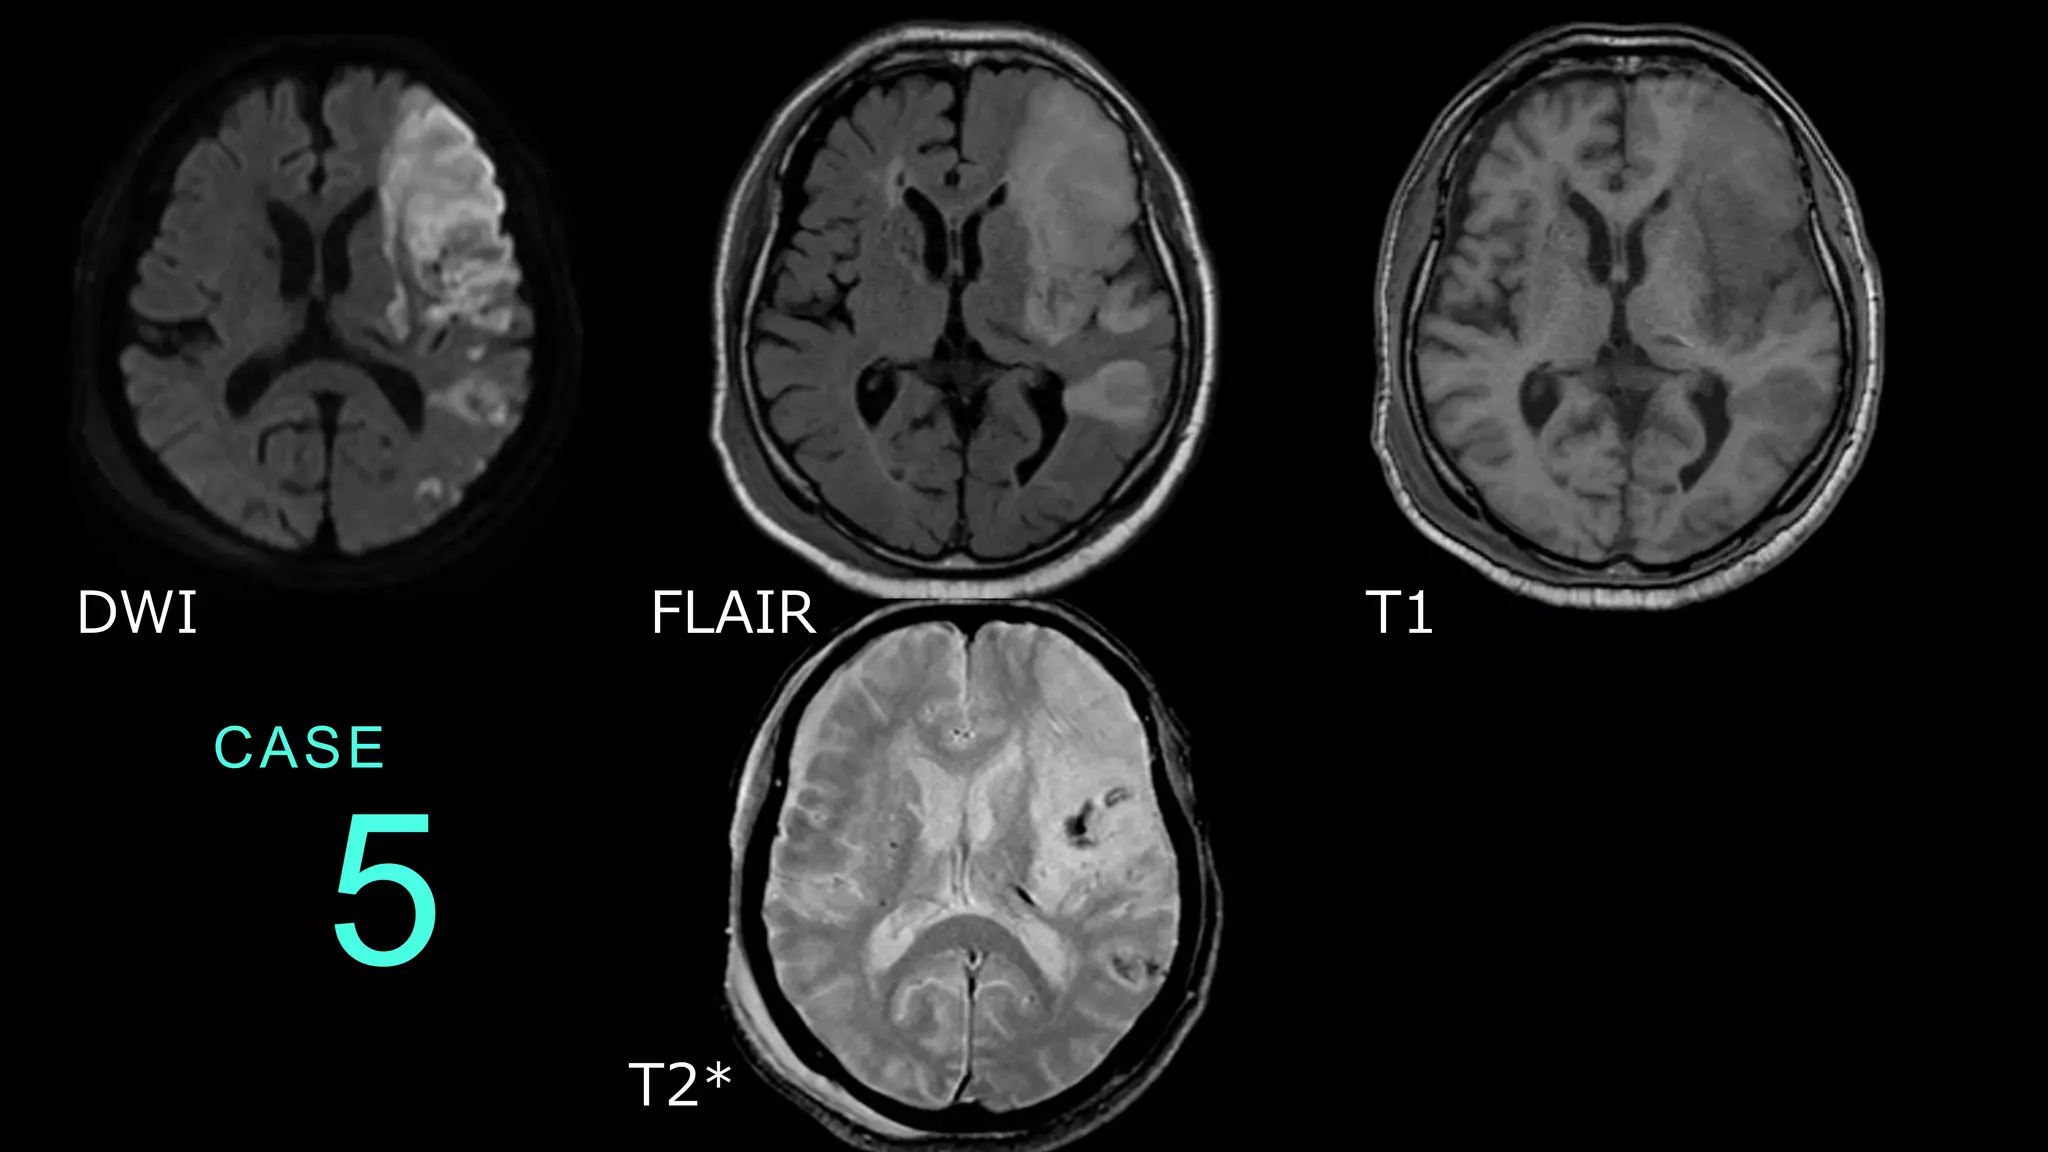

CASE 5 DWI FLAIR T1 T2*

CASE 5 DWIでは左の前頭葉を中心に、皮質を含んだ白質に広 範な高信号病変を認める。同病変はFLAIRでHIGH、 T1WIでLOWである。数日経過した亜急性期の脳梗塞 病変疑いである。 DWI FLAIR

CASE 5 T2*では、DWIでの信号変化を認める病変の内部に低 信号病変を認め、出血病変の合併が示唆される。 DWI T2*

CASE 5 DWI→FLAIR→T1まで信号変化を認めるので、時間の たった脳梗塞病変だとわかる。また、T2*で出血病変 が指摘できた。T2*がなければ判断は難しいので、こ こでは出血性病変の指摘にT2*が役に立った。 DWI FLAIR